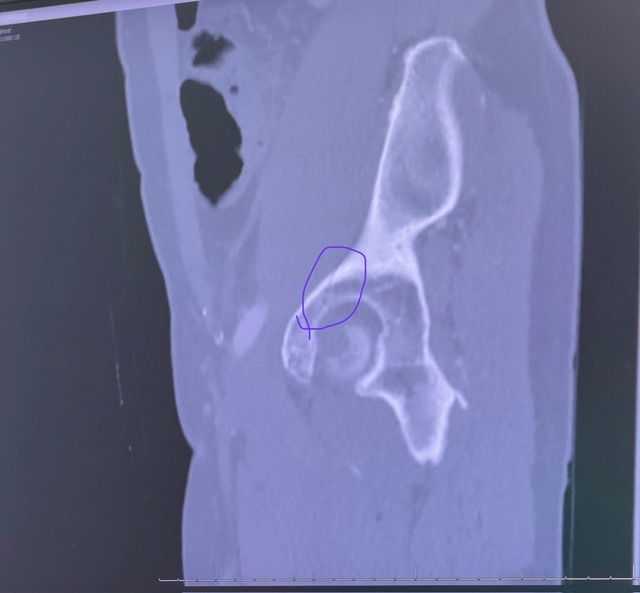

On March 14th, local friend and avid cyclist Luis Pagan was finishing his usual Saturday endurance training ride in Key Biscayne. After coming down the Rickenbacker Bridge, he accidentally hit something on the bike lane and unfortunately lost control of the handlebar, causing him to fall off the bike at high speed. Other cyclists in the area noticed he was hurt and offered immediate assistance. Paramedics arrived shortly after and transferred him to the ER at Jackson Memorial Hospital. Luis was seen by multiple doctors and specialists, including an orthopedic surgeon and trauma team, who confirmed he has a fractured hip, dislocated shoulder, sprained wrist, and multiple skin burn lacerations.

Luckily, Luis did not suffer any head injuries. However, CT scans show that he will need further examination (MRI) and treatment for his injured shoulder and fractured hip. After being discharged from the hospital, he has been instructed not to put any weight on his right leg for at least six weeks and then it will require several weeks of physical therapy . Please support Luis' recovery journey with any donations so that he can get a speedy recovery and back on his feet. The funds raised will go toward medical bills, living expenses, and therapeutic items to support his recovery.